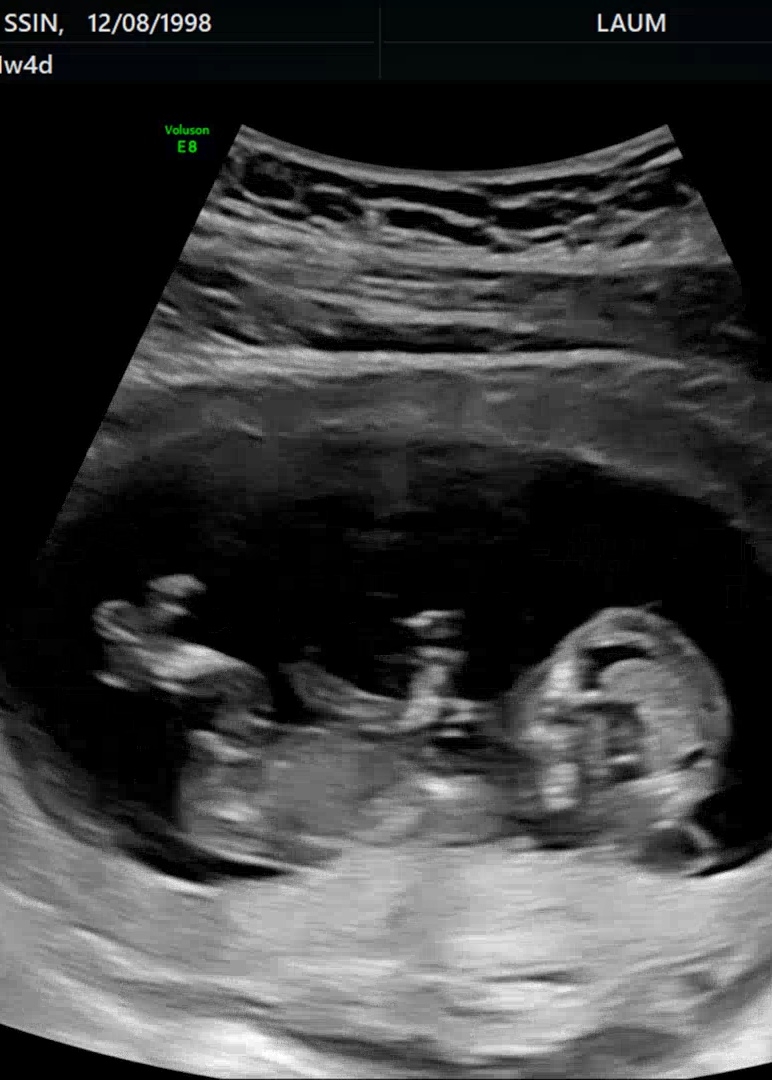

11주+4 각도법 봐주세요

안녕하세요 ~Nub는 어디예요?